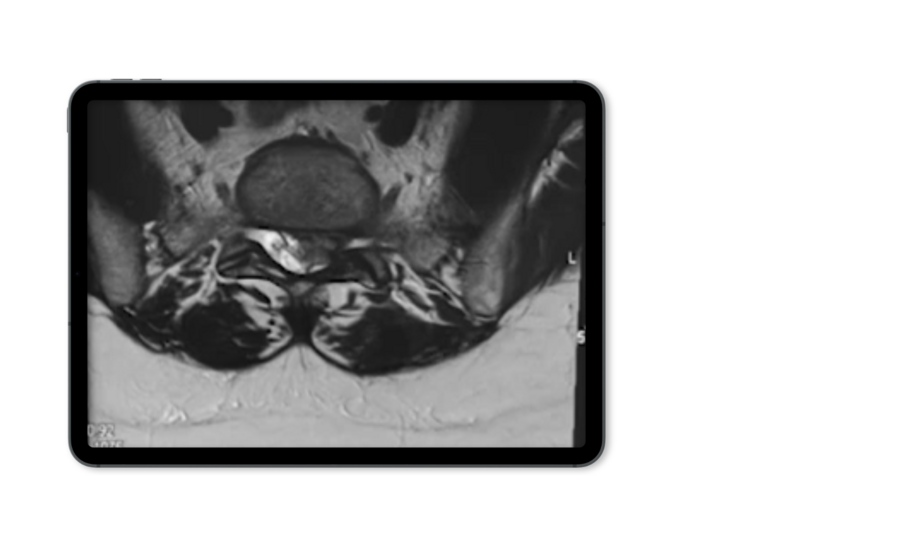

椎間板ヘルニアは、椎間板の一部が外層の裂け目から突出し近傍の神経構造を圧迫する疾患で、様々な問題を引き起こす可能性があります。これにより、痛み、痺れ、筋力低下が生じる可能性があります。治療の選択肢としては、理学療法、疼痛管理、そして重症の場合は手術などがあります。